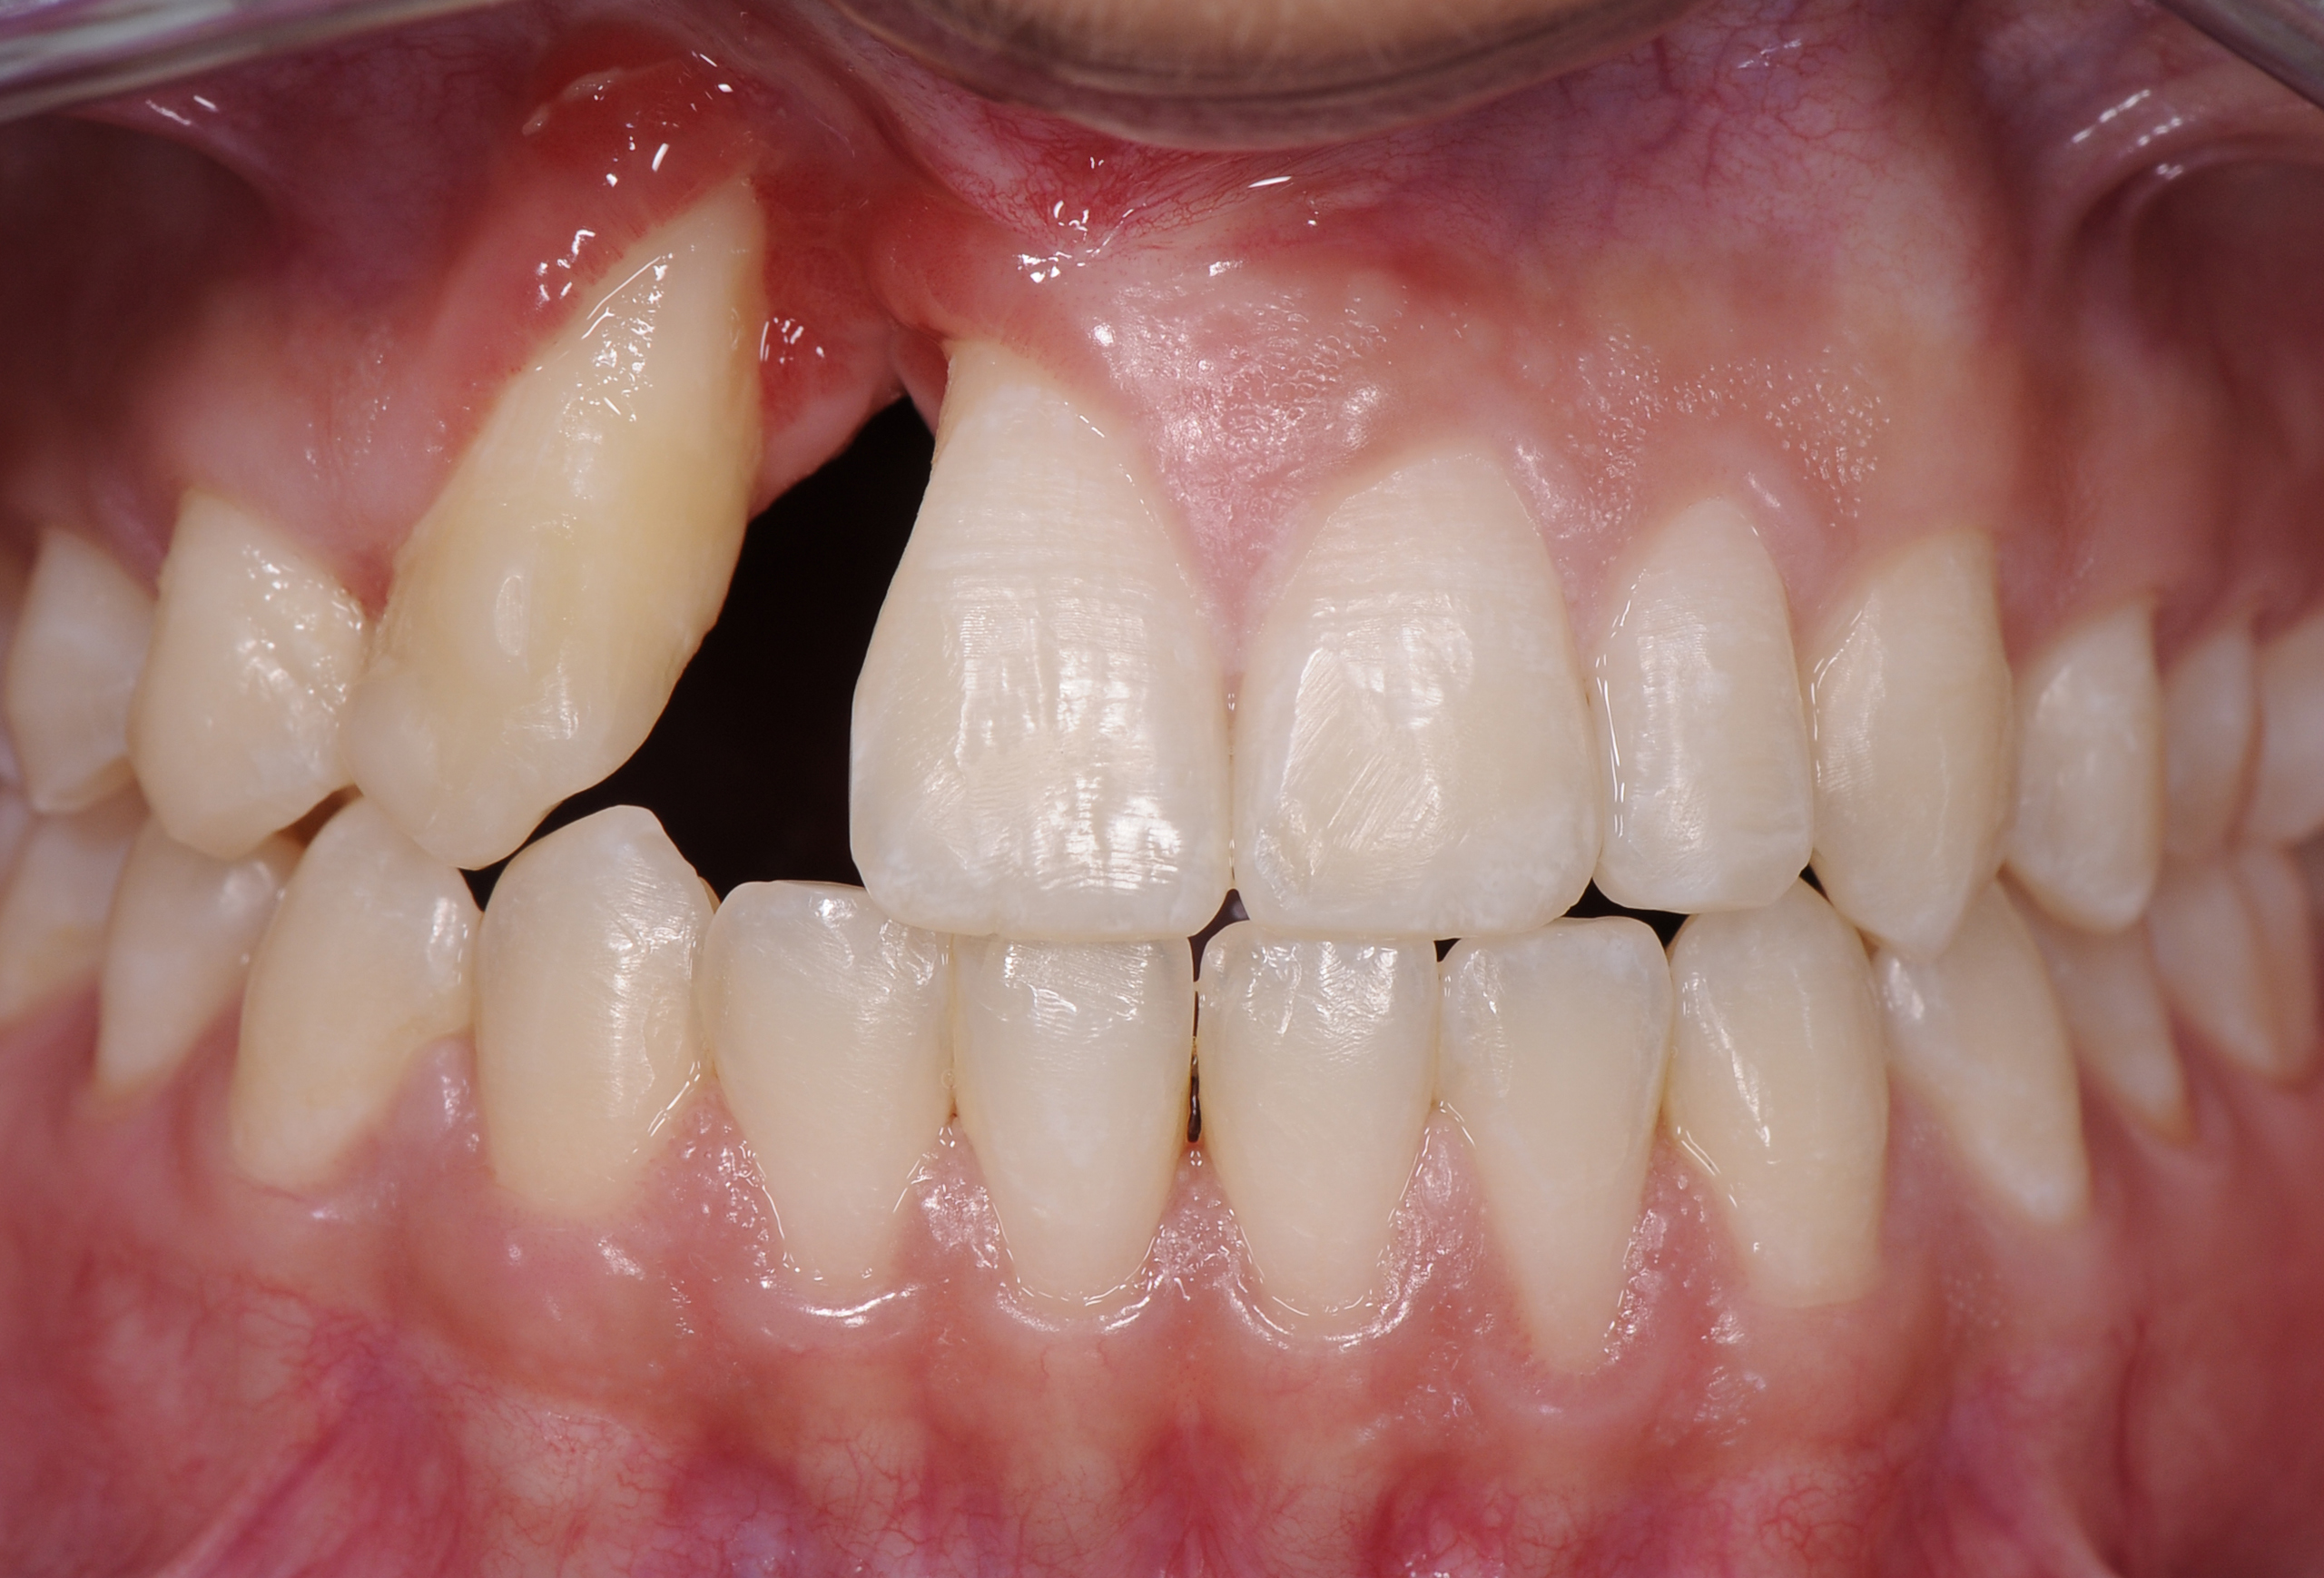

A healthy 20-year-old woman presented to the author’s office requesting treatment for a large defect in the area of missing tooth No. 7. She exhibited a high smile line that revealed a clearly visible deformity, associated with pain and sensitivity on teeth Nos. 6 and 8 and in the area of tooth No. 7 (Figure 1). Although the patient wore a modified Essix retainer, the defect was still visible because of the magnitude of tissue loss and the revealing nature of her smile.

The patient reported previous comprehensive orthodontic therapy, part of which included the creation of adequate space for replacement of the congenitally missing maxillary right lateral incisor. After completion of orthodontic therapy, implant placement and bone grafting were performed in the area of No. 7. Unfortunately, both procedures failed, resulting in a large hard- and soft-tissue defect. A subsequent attempt to perform bone augmentation was also unsuccessful and, instead, resulted in a larger deficit and increased recession on teeth Nos. 6 and 8. After a recommendation to attempt a third bone graft, the patient decided to seek alternative options.

Fig 1. The patient presented with a large deformity stemming from a congenitally missing maxillary right lateral incisor.

Figure 1

Fig 2. A failed implant and bone-graft procedures had resulted in a substantial iatrogenic gingival-alveolar defect.

Figure 2